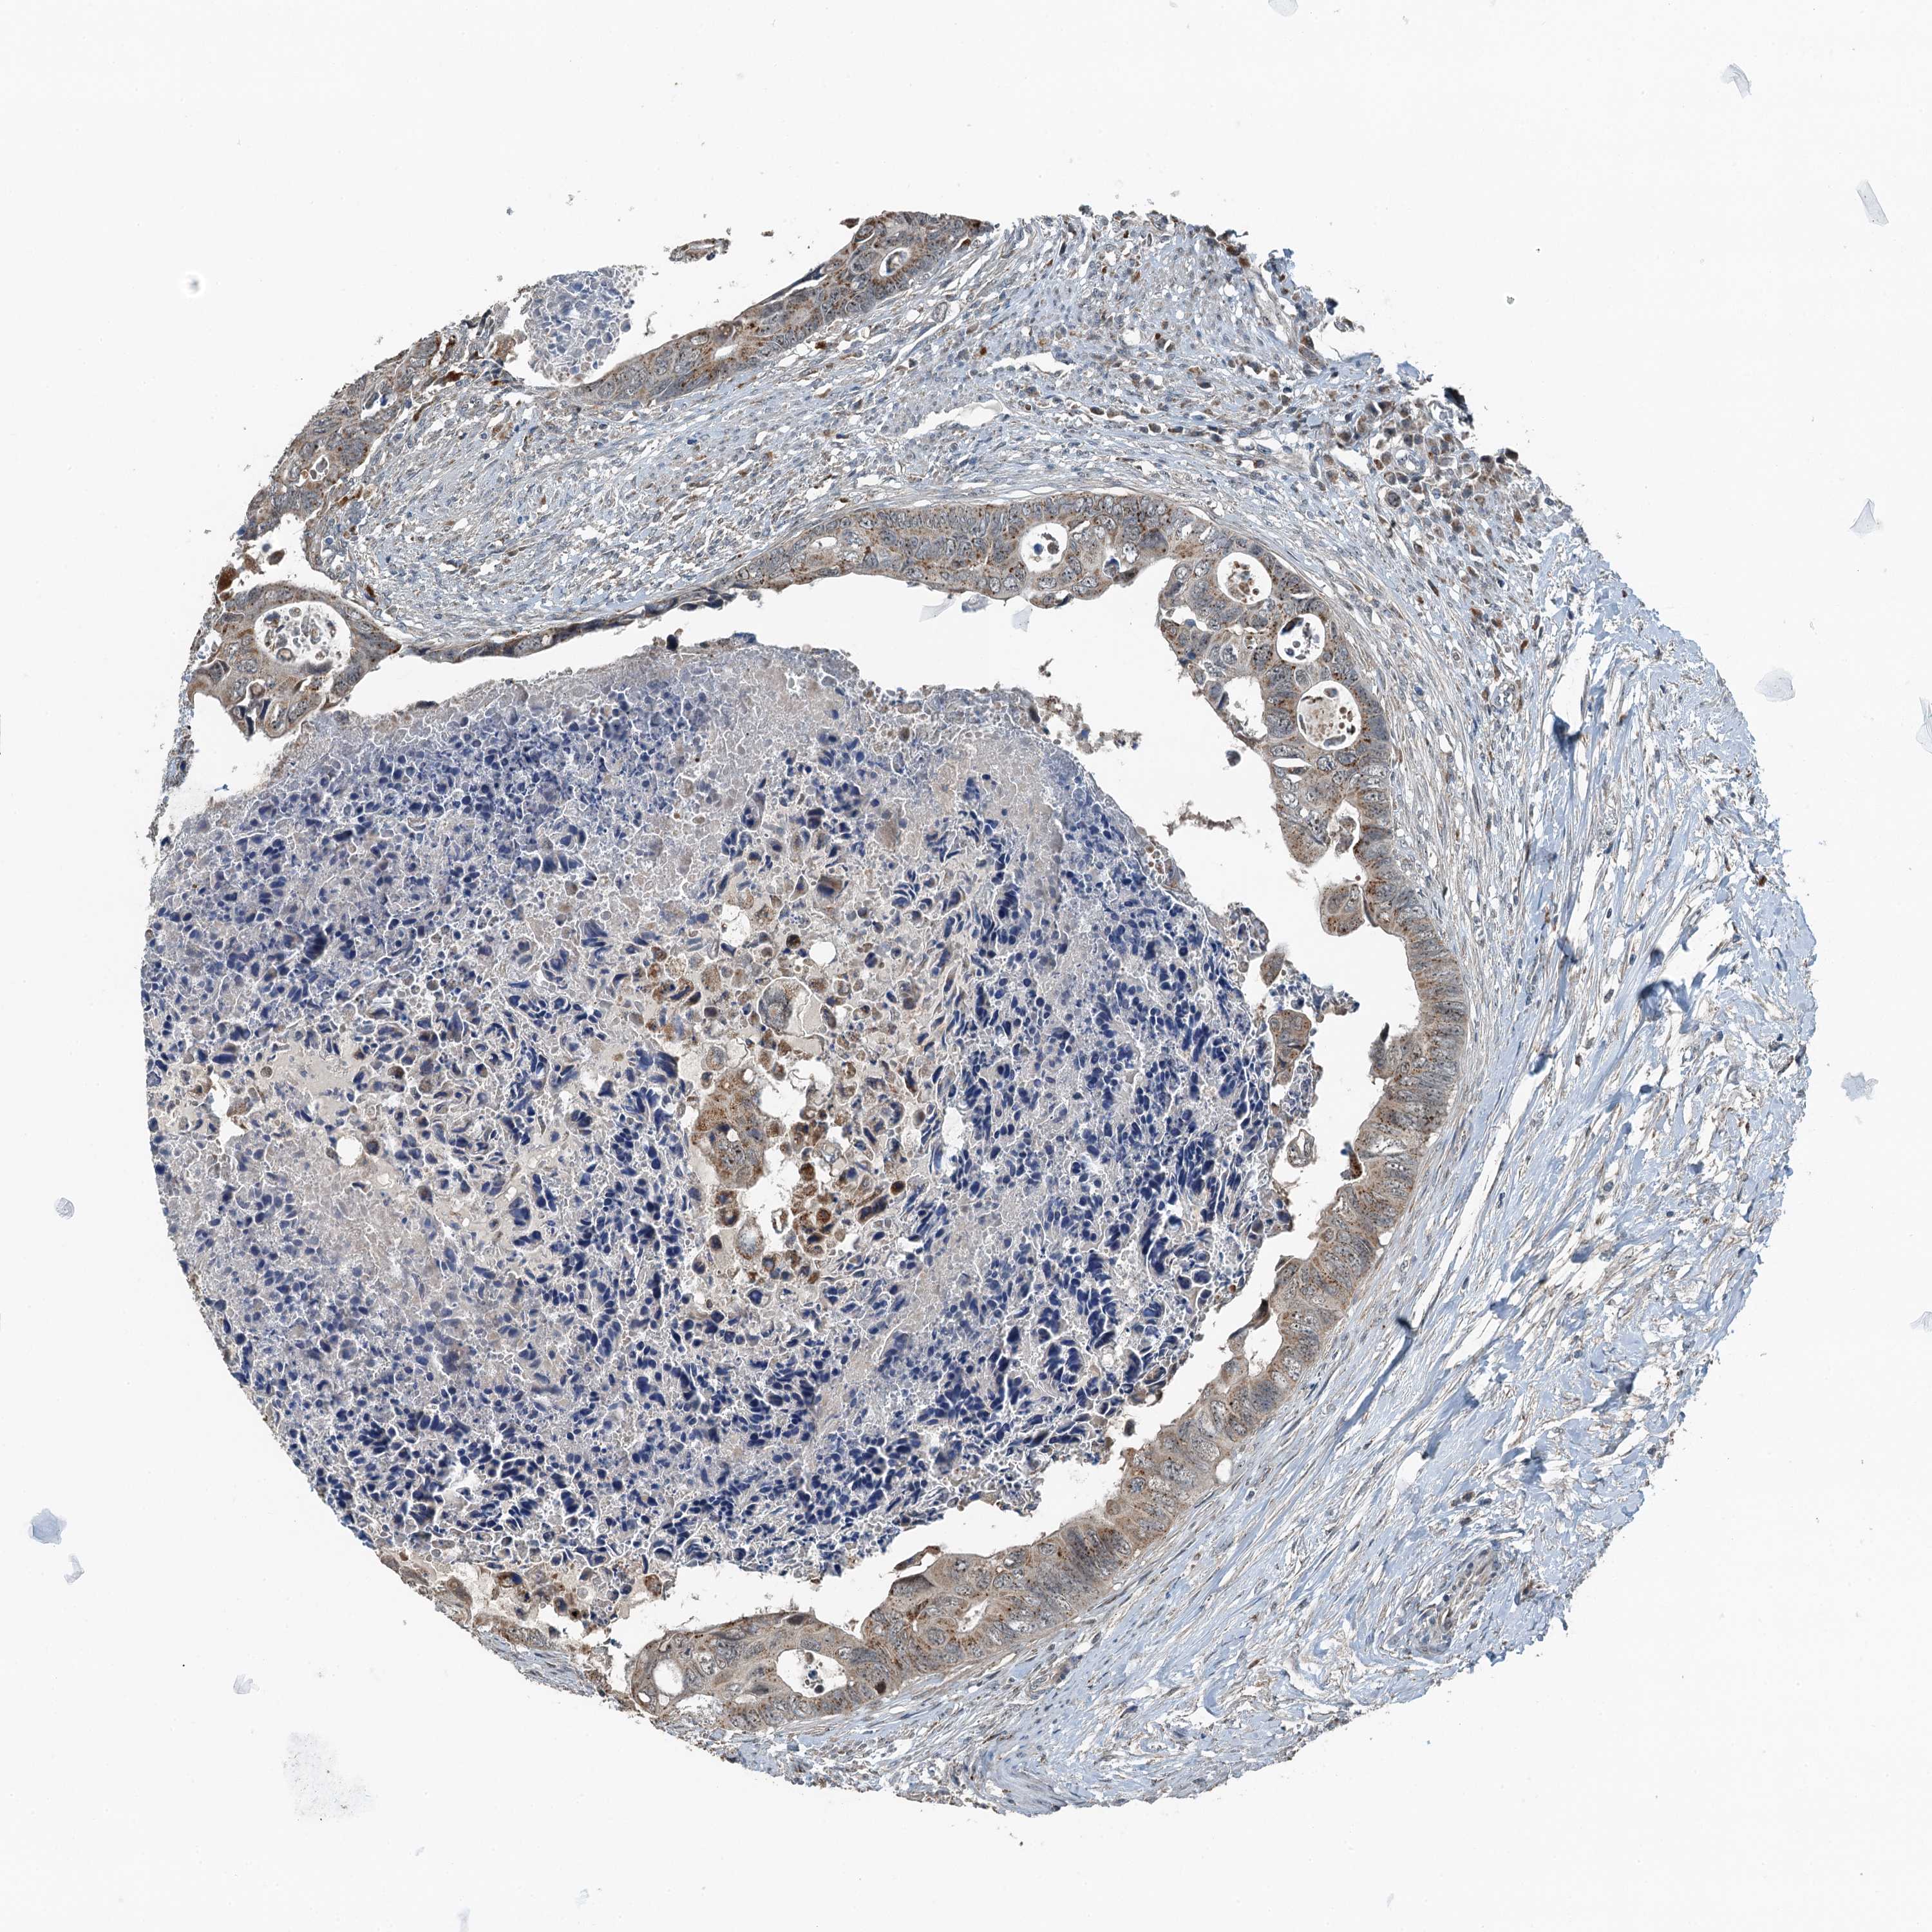

CANCER COLORECTAL CANCER Show tissue menu

Colorectal cancer

Human cancer

Colon adenocarcinoma